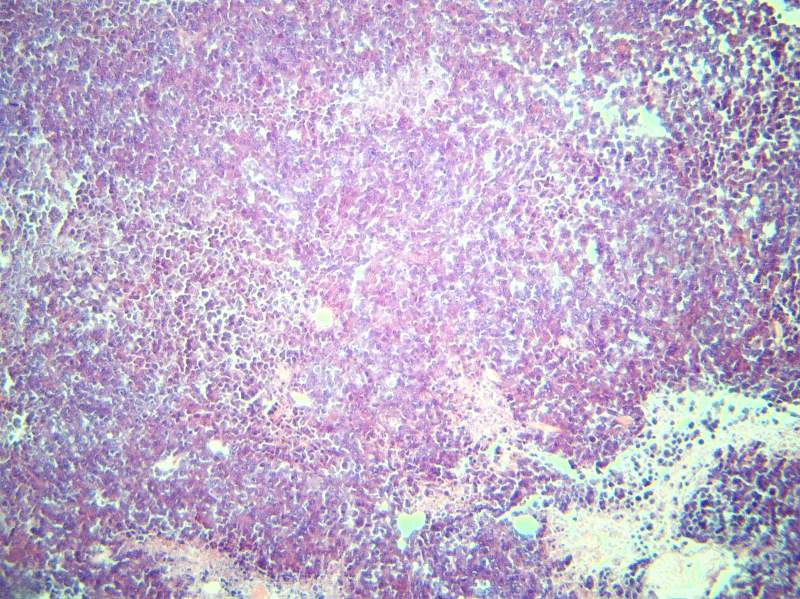

СÊóÆ¢ÔàºÍÖ×Áö×éÖ¯HEȾɫ½á¹ûÃèÊö

×î½üÔÚ×öÒ©ÀíʵÑ飬¶ÔСÊóµÄÆ¢ÔàºÍÖ×Áö×éÖ¯½øÐÐÁËHEȾɫ£¬¿àÓÚ¶ÔÆ¢Ôà½á¹¹²»Á˽ⲻ»á¶Ô½á¹û½øÐзÖÎö£¬ÌØÏò´ó¼ÒÇóÖú£¬Íò·Ö¸Ðл Æ¢ÔàµÍ±¶ Æ¢Ôà¸ß±¶ Æ¢ÔàµÍ±¶ Æ¢Ôà¸ß±¶ Ö×Áö×éÖ¯µÍ±¶ Ö×Áö×éÖ¯¸ß±¶ |